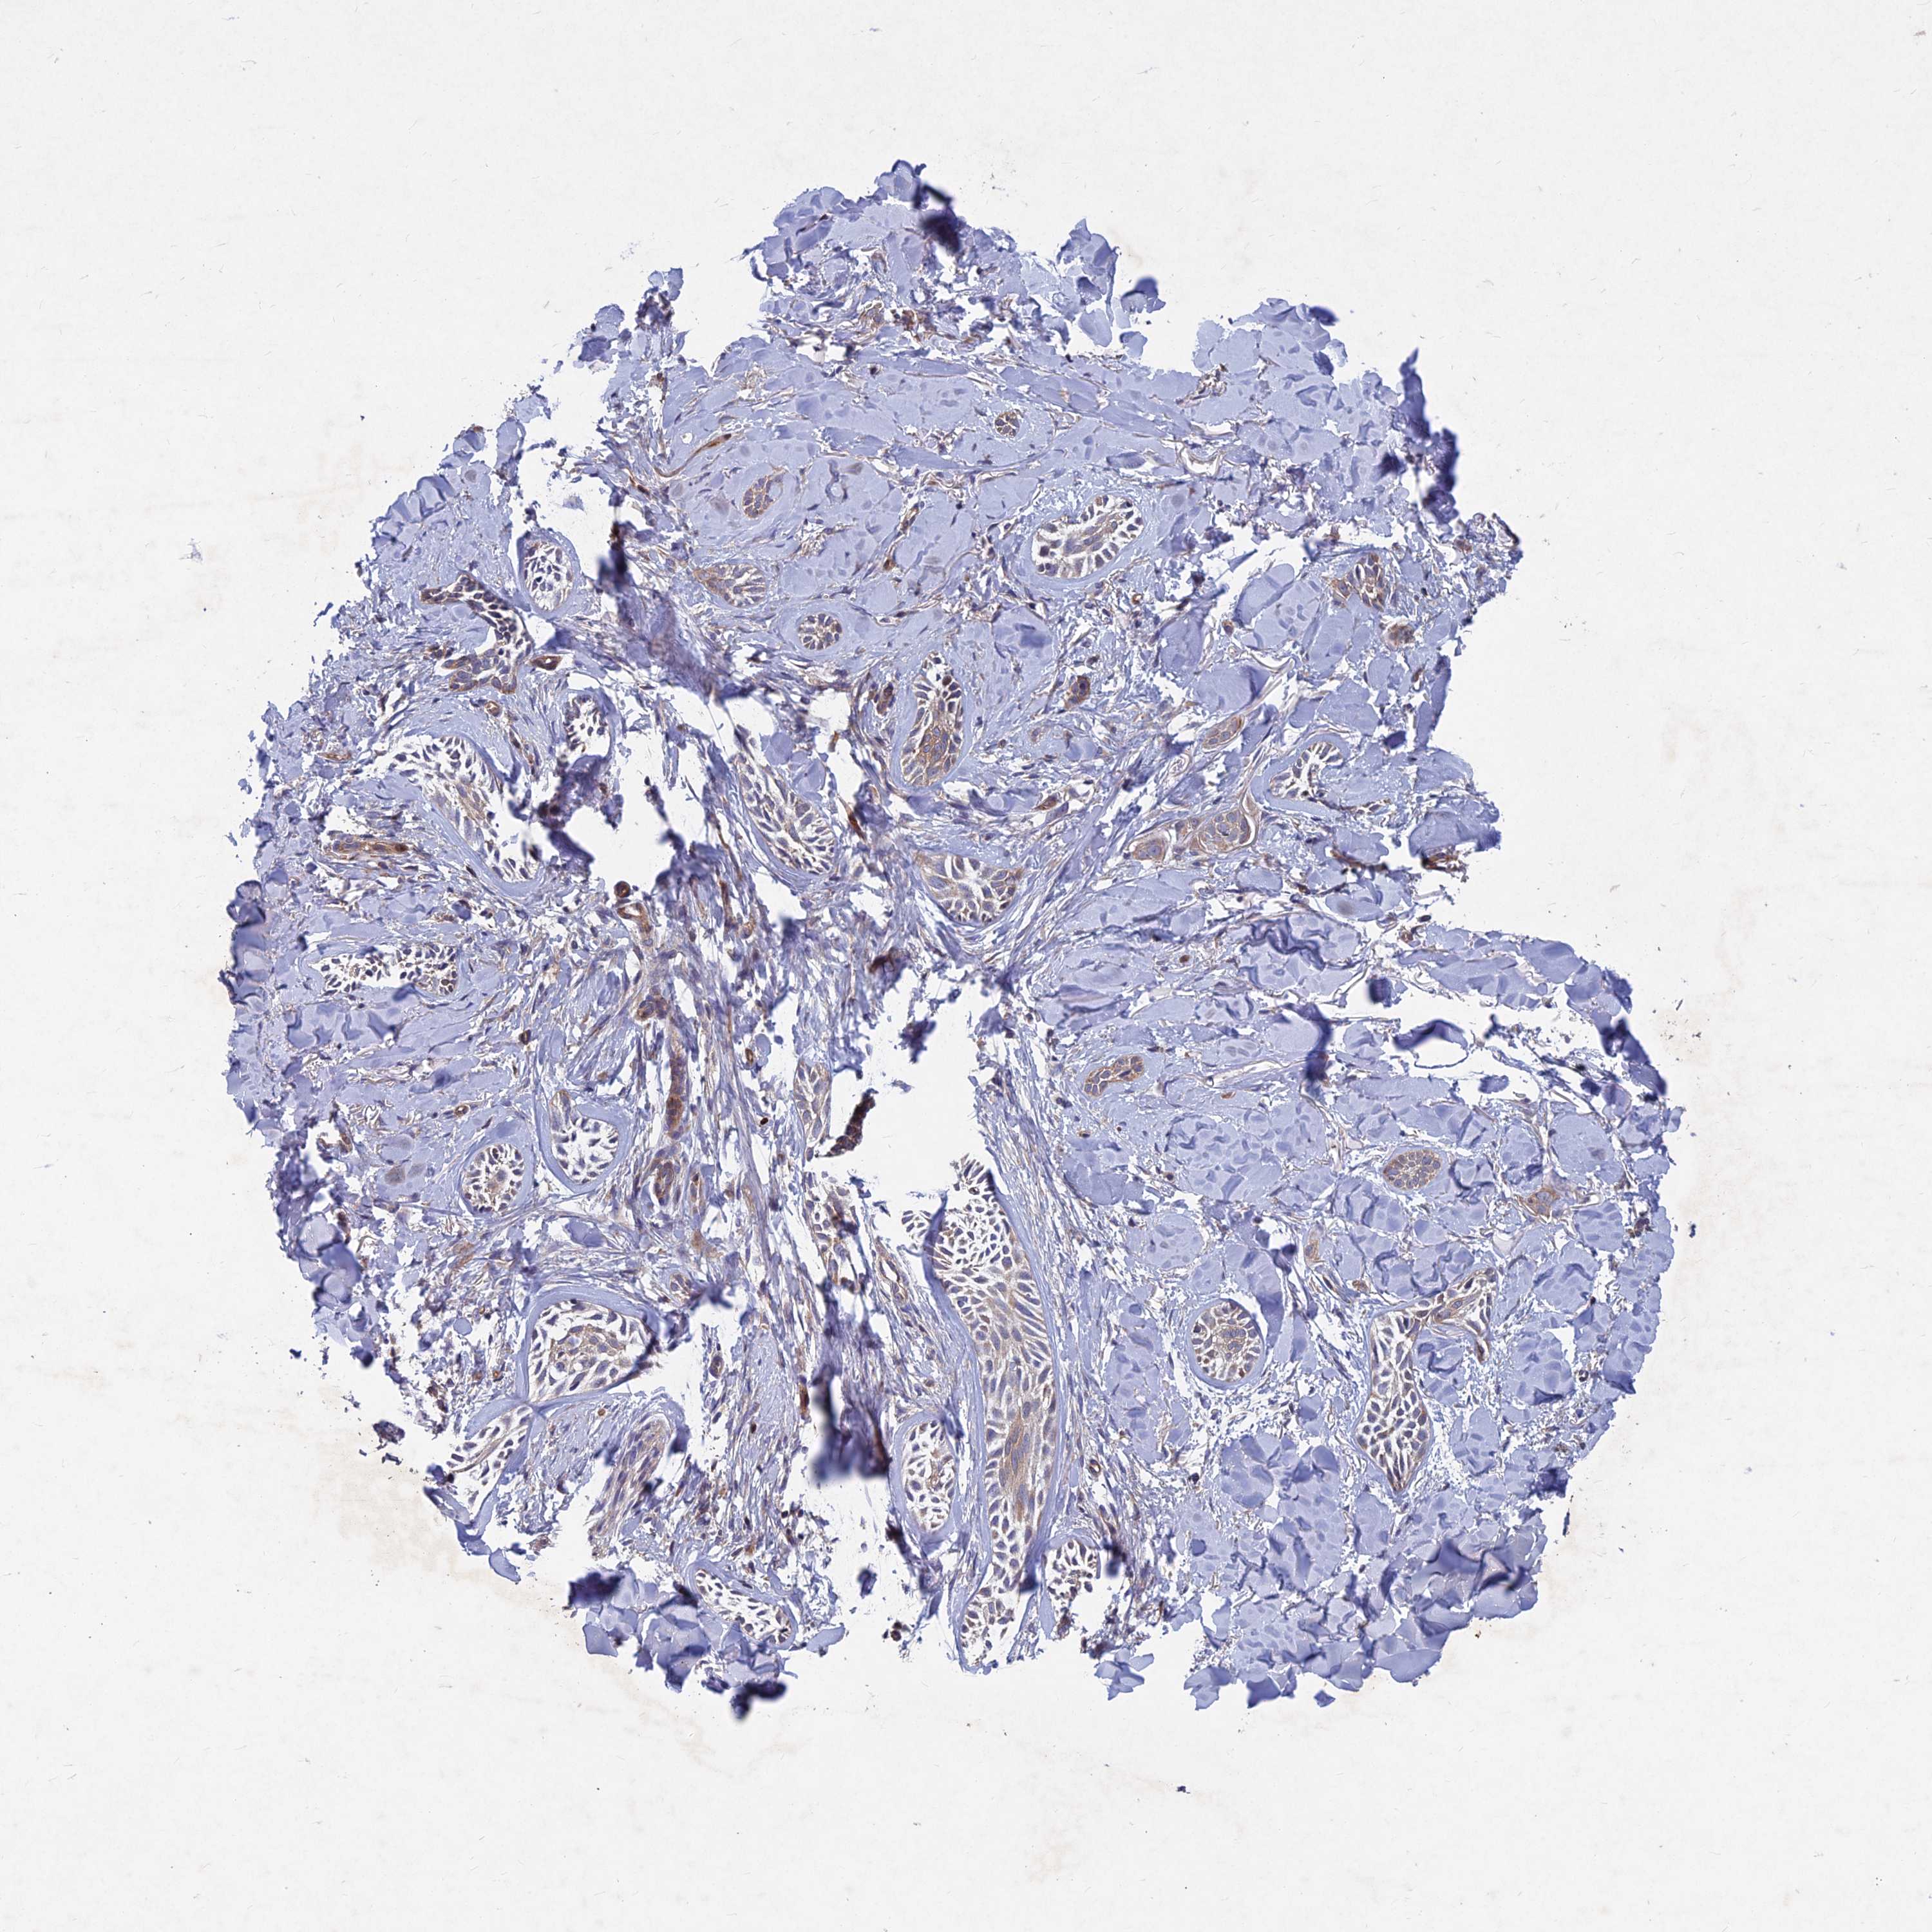

SKIN CANCER - Protein expressioni

A mouse-over function shows sample information and annotation data. Click on an image to view it in a full screen mode. Samples can be filtered based on level of antibody staining by selecting one or several of the following categories: high, medium, low and not detected. The assay and annotation is described here.

Antibody staining in the annotated cell types in the current human tissue is reported as not detected, low, medium, or high, based on conventional immunohistochemistry profiling in selected tissues. This score is based on the combination of the staining intensity and fraction of stained cells.

Each image is clickable and will lead to virtual microscopy that enables deeper exploration of all samples and also displays staining intensity scores, fraction scores and subcellular localization as well as patient and tissue information for each sample.

Antibody HPA039613

Basal cell carcinoma